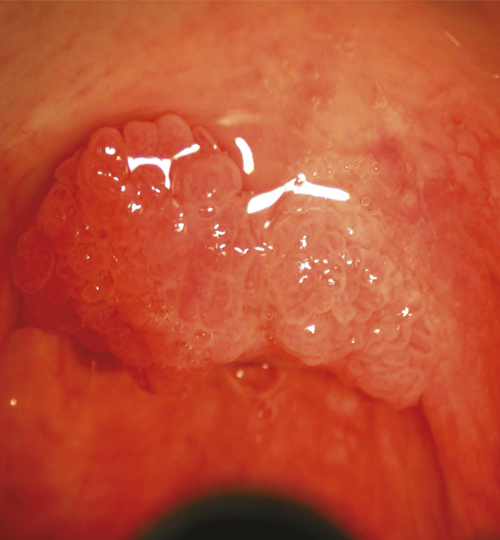

Avec plus de 18 000 cas annuels, les cancers des voies aérodigestives supérieures (VADS) représentent le 5e cancer le plus fréquent en France, le tabac et l’alcool étant les principaux facteurs de risque. En parallèle, la pathogénicité des papillomavirus humains a été mise en évidence, avec une part croissante de cancers des VADS liés à cette infection, d’où l’importance de la vaccination en prévention.

de Mones del Pujol E. Vaccination anti-papillomavirus et prévention des cancers de l’oropharynx.  Rev Prat 2022;72(10);1078-9.